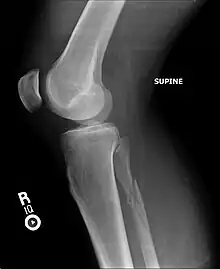

Radiographie d'une fracture du péroné (précisément, une fracture de Maisonneuve).